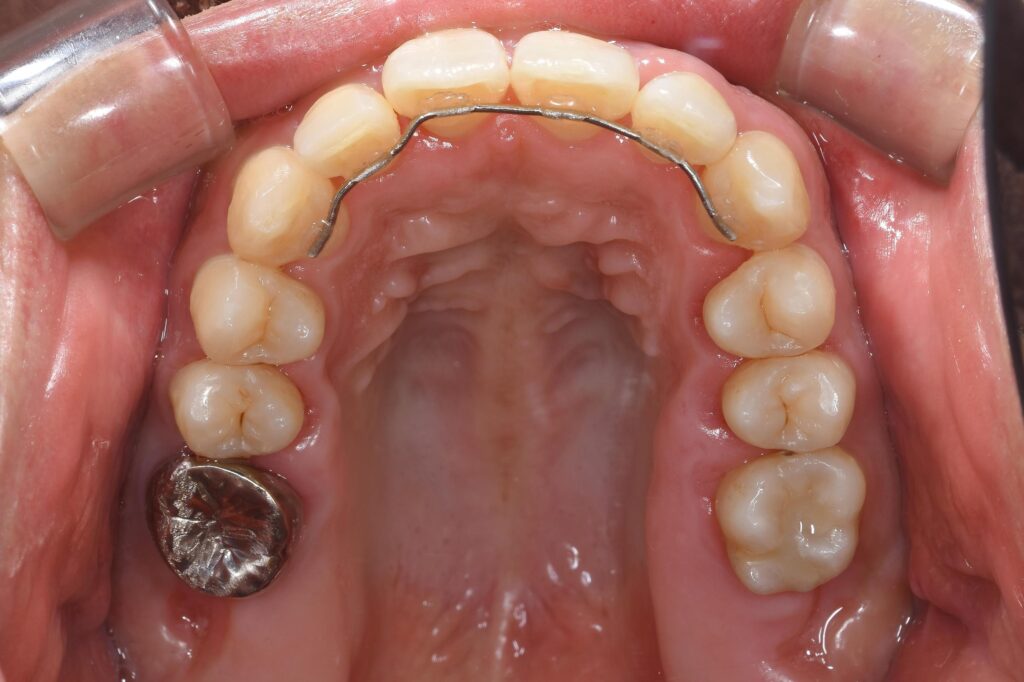

以下に術後写真です。

【術後(矯正終了後)】

治療期間は約1年弱。

矯正終了後には、保定装置(リテーナー)が必要です。

保定装置とは、矯正終了後に後戻りしないように何か装置を必要とします。

今回は裏側に針金を固定装置として選択し、接着剤で固定しております。

歯並びを改善したことで、歯磨きもしやすい環境を獲得することができ、虫歯リスクも軽減できたと思います。